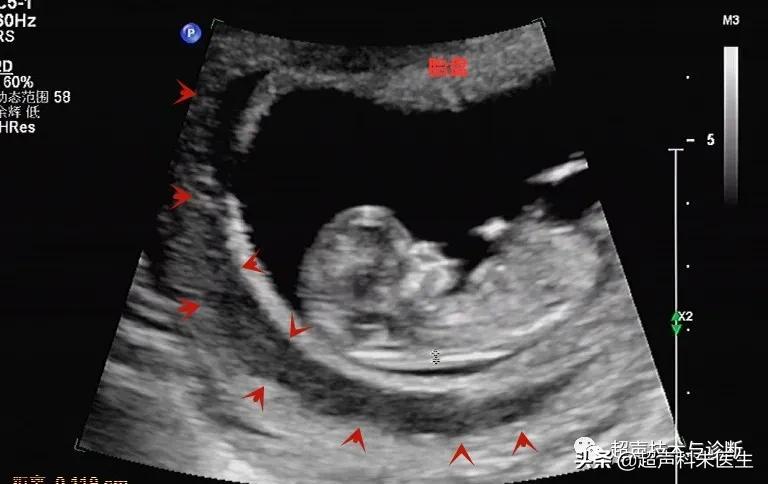

出现绒毛膜下血肿的孕妇,仅有20%会出现阴道不规则流血或下腹部疼痛的症状,而其余大多数绒毛膜下血肿是在超声检查中发现的,其超声表现为:子宫壁和胎膜(或孕囊)之间的无回声区,多位于胎盘下缘至宫颈内口间,以弧形或新月形多见,若血肿较多或血肿形成时间较长时,内可见点、絮状弱回声及条带状强回声,彩色多普勒超声检查:血肿内无血流信号。

根据绒毛膜下血肿的大小和范围,可对其进行定量分型:①小型血肿:妊娠囊周围绒毛膜下血肿的长度小于妊娠囊周长的20%;②中型血肿:妊娠囊周围绒毛膜下血肿的长度为妊娠囊周长的20~50%;③大型血肿:妊娠囊周围绒毛膜下血肿的长度大于妊娠囊周长的50%,或血肿的容积(长x宽x高÷2)>30ml。

接下来我们来看看具体病例: